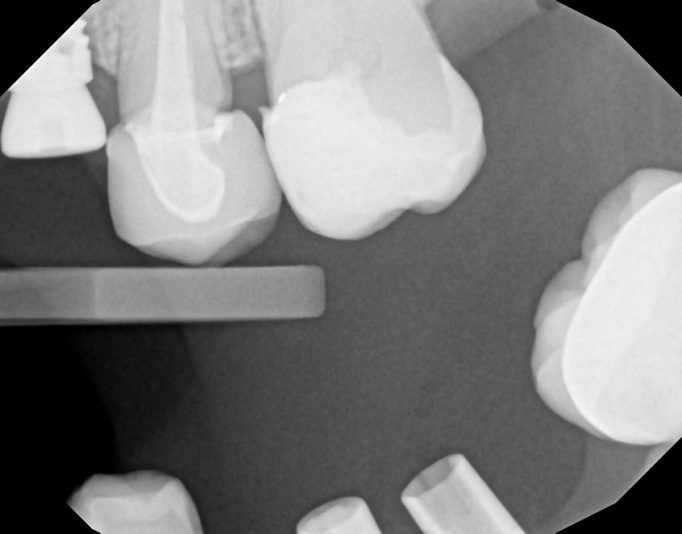

Hey guy, I’m still pretty new to implants. I’ve placed about 30. Looking for suggestions to improve. This is my most recent one. I chose 9 mm implant due to the proximity to the nerve. My main goal was to engage natural bone beyond the apex of the socket without getting too close to the nerve. I used the Densah burs, mostly in OD mode. and…